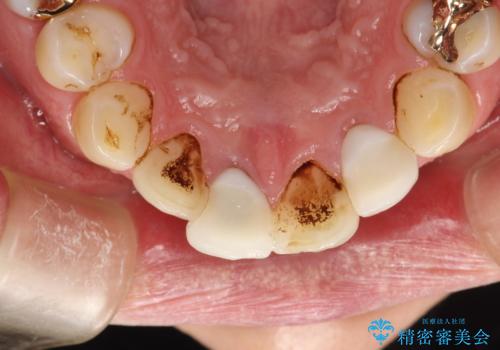

- 矯正治療前にホワイトニングがしたいとのことで来院されました。

処置前クリーニングとオフィスホワイトニングのエクセレントコースを行いました。

処置前クリーニングとオフィスホワイトニングのエクセレントコースを1回行いました。

この患者様は、歯科矯正に1、2年かかり矯正中はホワイトニングをすることが出来ないため、歯を白くしてから矯正治療にすすみたいとのことでオフィスホワイトニングを行いました。1回の施術で2.3トーン白くなり、とても白くなりました。ホワイトニングは何度も重ねて白くしていくのですが、1度で満足のいく色見になったため一旦様子を見ることにしました。